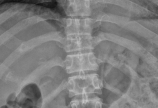

【脊柱其他】胸椎多椎体病变,如果诊断和治疗?

病情概述: 女,46岁,黎族,海南三亚市人。主诉:胸背部间断疼痛4年余。患者于2009年1月起无明显诱因出现胸背部疼痛,以左侧胸椎旁肌肉为主,先后转移至右侧椎旁肌肉,脊正中及双侧胸10、11肋骨,并放射至腹部,2009年12月患者因右侧腋窝肿物就诊,行CT检查提示:1.颈… [详情]